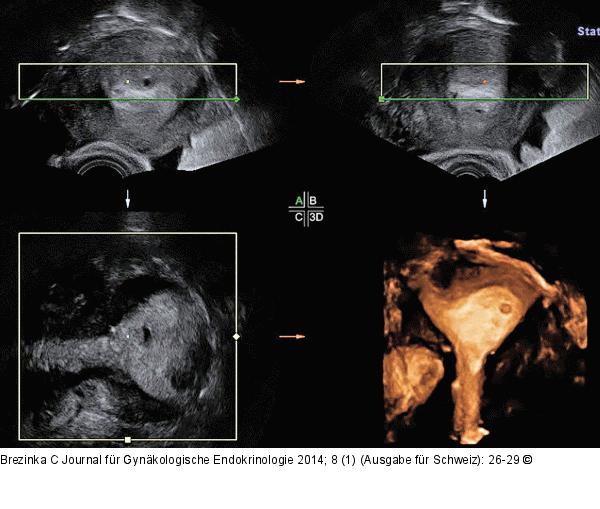

Abbildung 1: Gyn-Ultraschall Ein 4 mm großer topischer Fruchtsack am 5. Tag der Amenorrhö im linken Anteil eines leichten Uterus arcuatus. So früh kann man noch keine Diagnose und keine Aussagen über die Prognose der Schwangerschaft machen. |

Ein 4 mm großer topischer Fruchtsack am 5. Tag der Amenorrhö im linken Anteil eines leichten Uterus arcuatus. So früh kann man noch keine Diagnose und keine Aussagen über die Prognose der Schwangerschaft machen. |